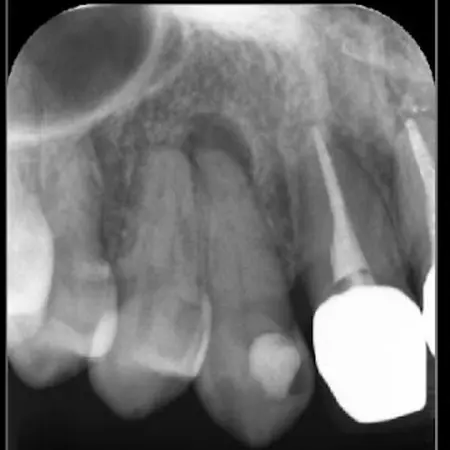

当院では、お口の中の健康とお口周りの美しさをトータル的に考えた治療を心がけています。歯科医院の目的は、虫歯・歯周病の歯の治療です。しかし最も力を入れるべきことは、虫歯や歯周病にならないための予防指導だと考えます。 プラークコントロールや歯の健康診断を定期的に受けることで大切な歯を守れるのです。丈夫で健康な歯は、何でも美味しく食べることができ、いつまでも若々しい口元と笑顔を保てます。当院の指導で、ご自分の歯で末永く健康にいきいきお過ごしいただきたいと思っています。